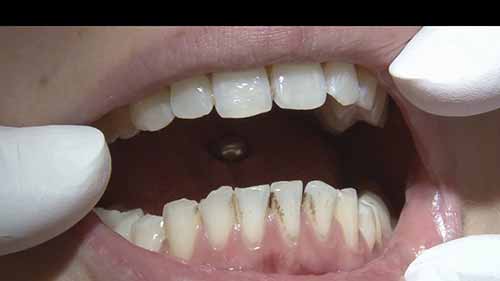

活根管治疗

时长:31 分钟

类别:口腔医学

简介:根管治疗术又称牙髓治疗,是牙医学中治疗牙髓坏死和牙根感染的一种手术。我们一起来看看医生利用根管显微镜,演示完整的根管治疗过程。